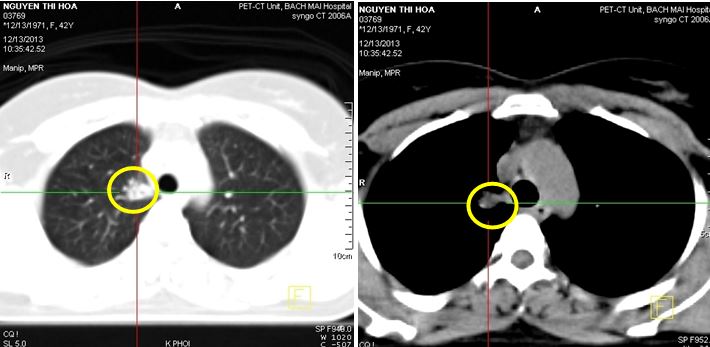

1. Chụp cắt lớp vi tính lồng ngực: Hình ảnh tràn dịch màng phổi phải, hạch trung thất (hình 1a)

Hình 1a: Hình ảnh chụp cắt lớp vi tính lồng ngực thấy tràn dịch khoang màng phổi phải (đầu mũi tên đỏ), khó đánh giá hạch trung thất (trong vòng tròn đỏ).

Hình 1b: Trên hình ảnh PET/CT sau 1 tháng điều trị thấy hạch trung thất kích thước 0,9 cm, max SUV=2,8 (đầu mũi tên đỏ), do bệnh nhân không chụp PET/CT trước điều trị nên khó đánh giá hạch trung thất mới xuất hiện sau điều trị hay hạch nhỏ đi sau điều trị, giả thiết hạch nhỏ đi sau điều trị phù hợp hơn do trên phim chụp CT ngực 64 dãy sau 5 tháng điều trị (xem hình số 10) không còn thấy hạch trung thất.